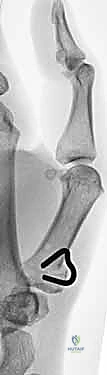

3. بضع العظم (The Osteotomy) - الخطوة الحاسمة

• تحت التوجيه المستمر بجهاز الأشعة السينية داخل غرفة العمليات (Fluoroscopy)، يقوم الدكتور هطيف بتحديد مكان القطع بدقة متناهية (عادة على بعد 1 سم من سطح المفصل).

• يتم إدخال أسلاك معدنية دقيقة (K-wires) كأدلة لتحديد زاوية القطع.

• باستخدام منشار جراحي دقيق متذبذب، يتم إزالة إسفين عظمي صغير (Wedge) من قاعدة العظم المشط، بحيث تكون قاعدة هذا الإسفين متجهة للخلف (ظهرياً).

• زاوية الإسفين تُحسب بدقة فائقة من قبل الدكتور هطيف لتناسب حالة المريض، وغالباً ما تتراوح بين 20 إلى 30 درجة من الإطالة.